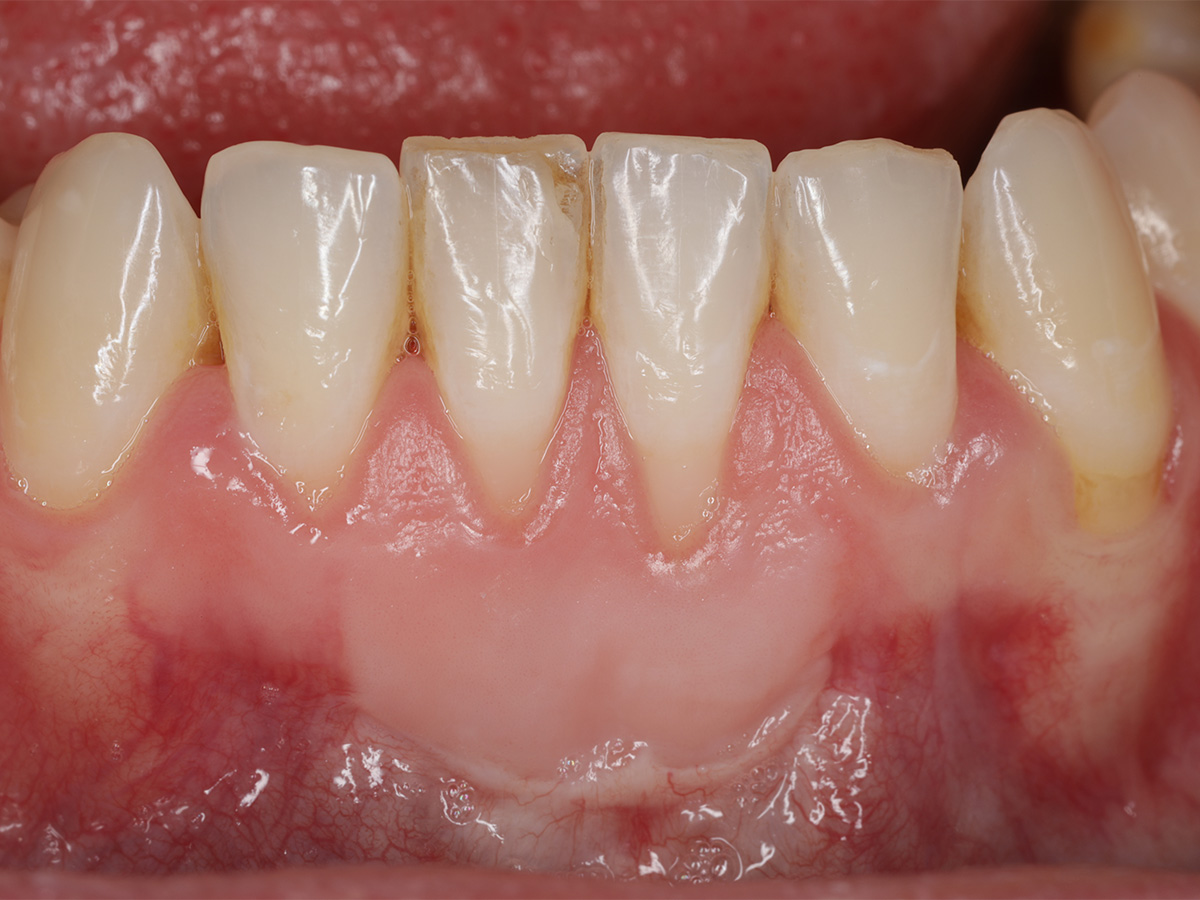

Die Heilung verlief komplikationslos und die Entfernung der Nähte und des Gewebeklebers erfolgten 14 Tage postoperativ. 13 Monate nach dem Eingriff zeigte sich ein signifikanter Zugewinn an befestigtem keratinisiertem Gewebe sowie eine deutliche Deckung der Rezessionen in regio 31/41.

Abbildung 5

Klinische Situation 13 Monate nach Weichgewebsaugmentation.